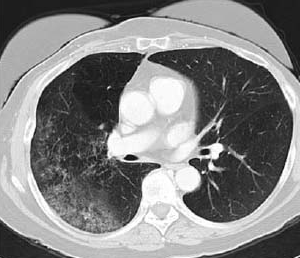

Bronchoalveolar cell carcinoma detected by CT (image provided by the American Thoracic Society).